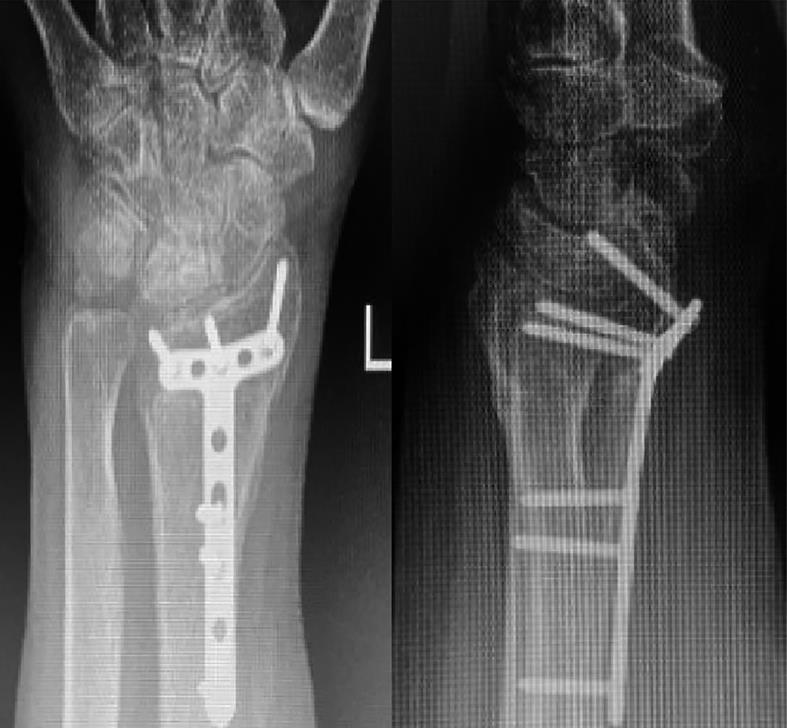

图2 术后X线片结果

Fig. 2 Postoperative X-ray